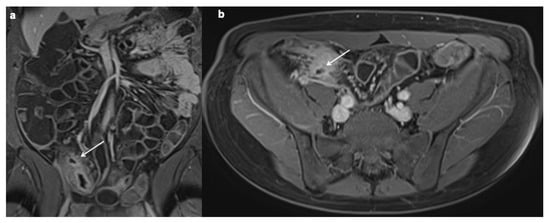

11. Imaging Findings Associated with Penetrating CD Inflammation and Complications

| Imaging findings associated with penetrating CD and complications |

| Sinus tract |

Fistula

|

| Inflammatory mass |

| Abscess |

| Free perforation |